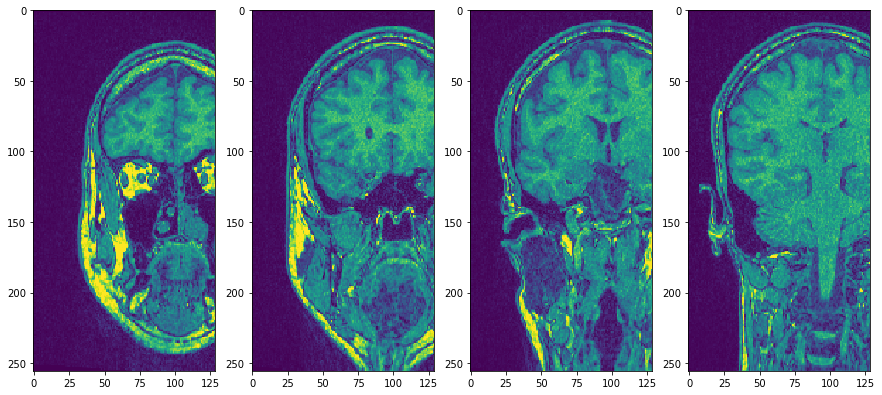

使用子图将它们并排放置

fig, axs = plt.subplots(1, 4, figsize=(15, 7))

cle.imshow(transposed_image[75], plot=axs[0])

cle.imshow(transposed_image[100], plot=axs[1])

cle.imshow(transposed_image[125], plot=axs[2])

cle.imshow(transposed_image[150], plot=axs[3])

../_images/c7f6aa8ebe01402e92cd9a40e380bf9cf1b1febdd7a6e15069da4e5756ff6e04.png